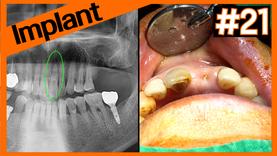

- 임플란트

OneGuide surgery on #36 after SP using LCR

OneGuide surgery on #46, 47 after SP using SureOss

#21, #23 Immediate Implant Placement

#16 Implant using OneCAS KIT without Bone graft after SP ...

Implants on #26 & #27 using OneCAS KIT after socket prese...

2 stage implant on #21 after socket preservation using A-...

Immediate implant & A-Oss Collagen graft using OneGuide &...

OneCAS on #16, #17 (Decision guide of final OneCAS drill ...

Re-implant on failed MS implant site using OneMS

OneGuide implants on #15, #16, #46 after SP using A-Oss C...

Fixation of OneGuide template using Vertical anchor & OneCAS

Immediate implant on #12 & dual zone graft

#16, #17 OneCAS & #14 GBR using A-Oss Collagen

#17 Implant using OneGuide on socket preservation(A-Oss +...

#16 & #17 Implant using OneGuide after flap elevation for...

#26 Implant using OneCAS on 3mm residual alveolar bone he...

Implant after socket preservation using A-Oss Collagen & ...

Implant on #12 & #22 using OneGuide after removal of PFM ...

Immediate implant on #32 & #42 using OneMS

Implant after socket preservation using A-Oss

Implant using OneCAS KIT after Socket Preservation using ...